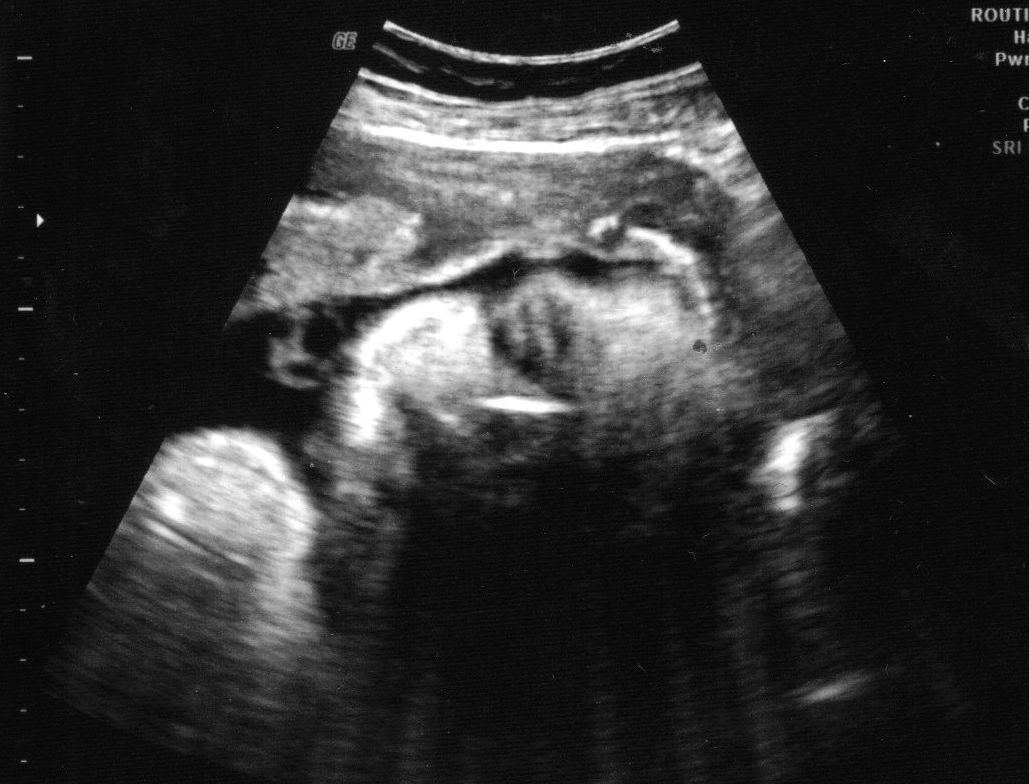

Went to the doc on Monday for one of my two weekly visits. We got another ultrasound and the (not so) little man is weighing in at 6lbs 14oz and is super long...and chunky! He is looking healthy and has dropped, so I am hoping he decides to come earlier than expected...like next week! Yeah, I know, wishful thinking.